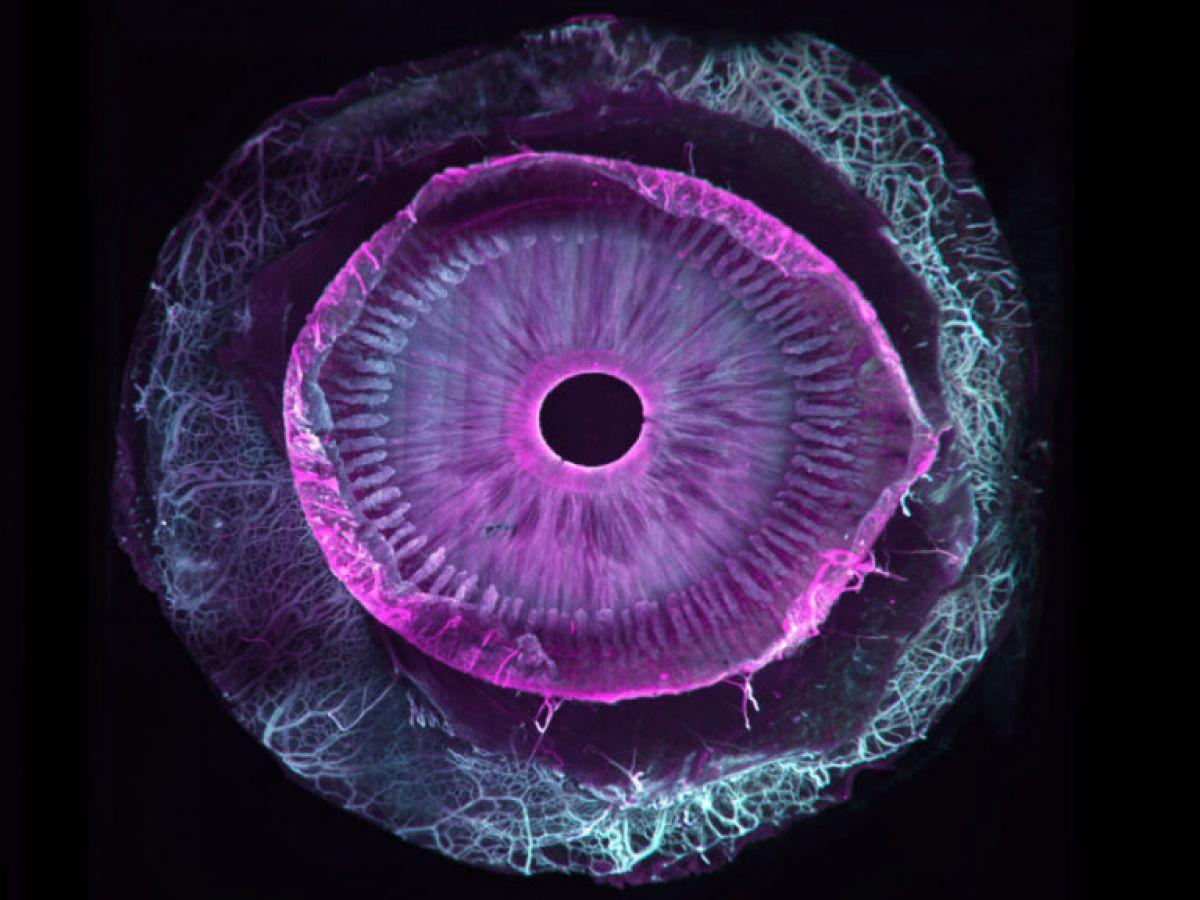

Africa-Press – Benin. Sept ans de travail pour une première mondiale : la transparisation (le fait de rendre transparent) d’un œil humain entier. Ce travail, tout juste publié dans la revue Communications Biology, est une collaboration franco-suisse entre, d’une part, Marie Darche, une ingénieure de recherche et membre de l’équipe du Pr Michel Paques à l’hôpital des Quinze-Vingts et à l’institut de la vision (Paris), et d’autre part ses collègues de l’institut Wyss (Genève).

Si les seconds se sont eux occupé du versant imagerie du projet grâce à un dispositif optique particulier, un microscope à feuillet de lumière (MesoSPIM), la biologiste s’est, elle, attaquée au versant « clearing », c’est-à-dire les étapes de transparisation permettant de transformer un échantillon biologique initialement opaque en une structure transparente. Comment ? Par différentes manipulations reposant sur une succession de bains dans des solvants organiques associées au marquage par des anticorps fluorescents.

Tout commence forcément avec des dons d’yeux, issus ici de donneurs américains morts, la législation française ne permettant pas ce type précis de dons (la banque française des yeux ne s’occupe que des cornées et pas d’œil entier). En pratique, toujours de petites sphères de six centimètres cube de volume, dont on ne soupçonne pas l’extraordinaire complexité ni l’hétérogénéité en lien avec les différentes couches de cellules, vaisseaux, nerfs, cellules immunitaires…

Car si d’autres équipes étaient parvenues par le passé à clarifier certains segments de l’œil, c’est bien ici la première fois qu’un œil entier est transparisé. « Au total, nous avons utilisé 25 yeux sains et allons prolonger nos travaux avec d’autres globes oculaires cette fois pathologiques et atteints de DMLA (dégénérescence maculaire liée à l’âge, ndlr), de glaucome et de myopie forte, le tout grâce au soutien d’associations de patients », précise la chercheuse, qui poursuit : « Nos travaux permettront une approche plus holistique des pathologies de l’œil tout comme un meilleur dialogue entre chercheurs et cliniciens pour mieux comprendre les maladies de l’œil et leurs mécanismes ».